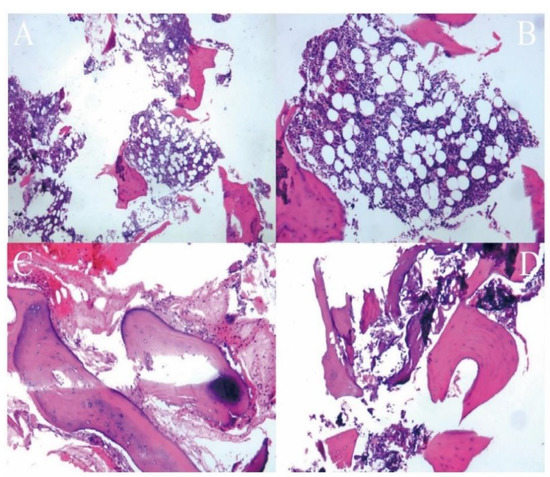

2. Materials and Methods

2.2. Surgical Technique

3. Results